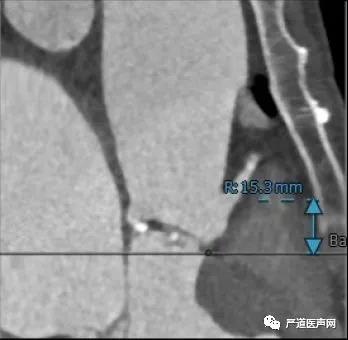

术前CT:

右冠开口高度 15.3mm